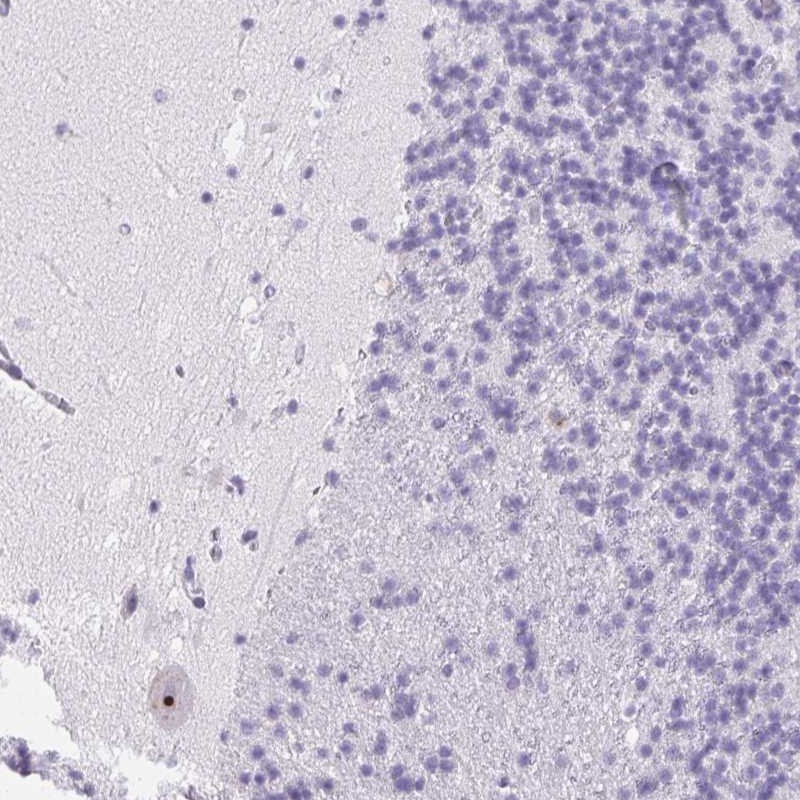

Immunohistochemical staining of human cerebellum shows strong nucleolar positivity in Purkinje cells.